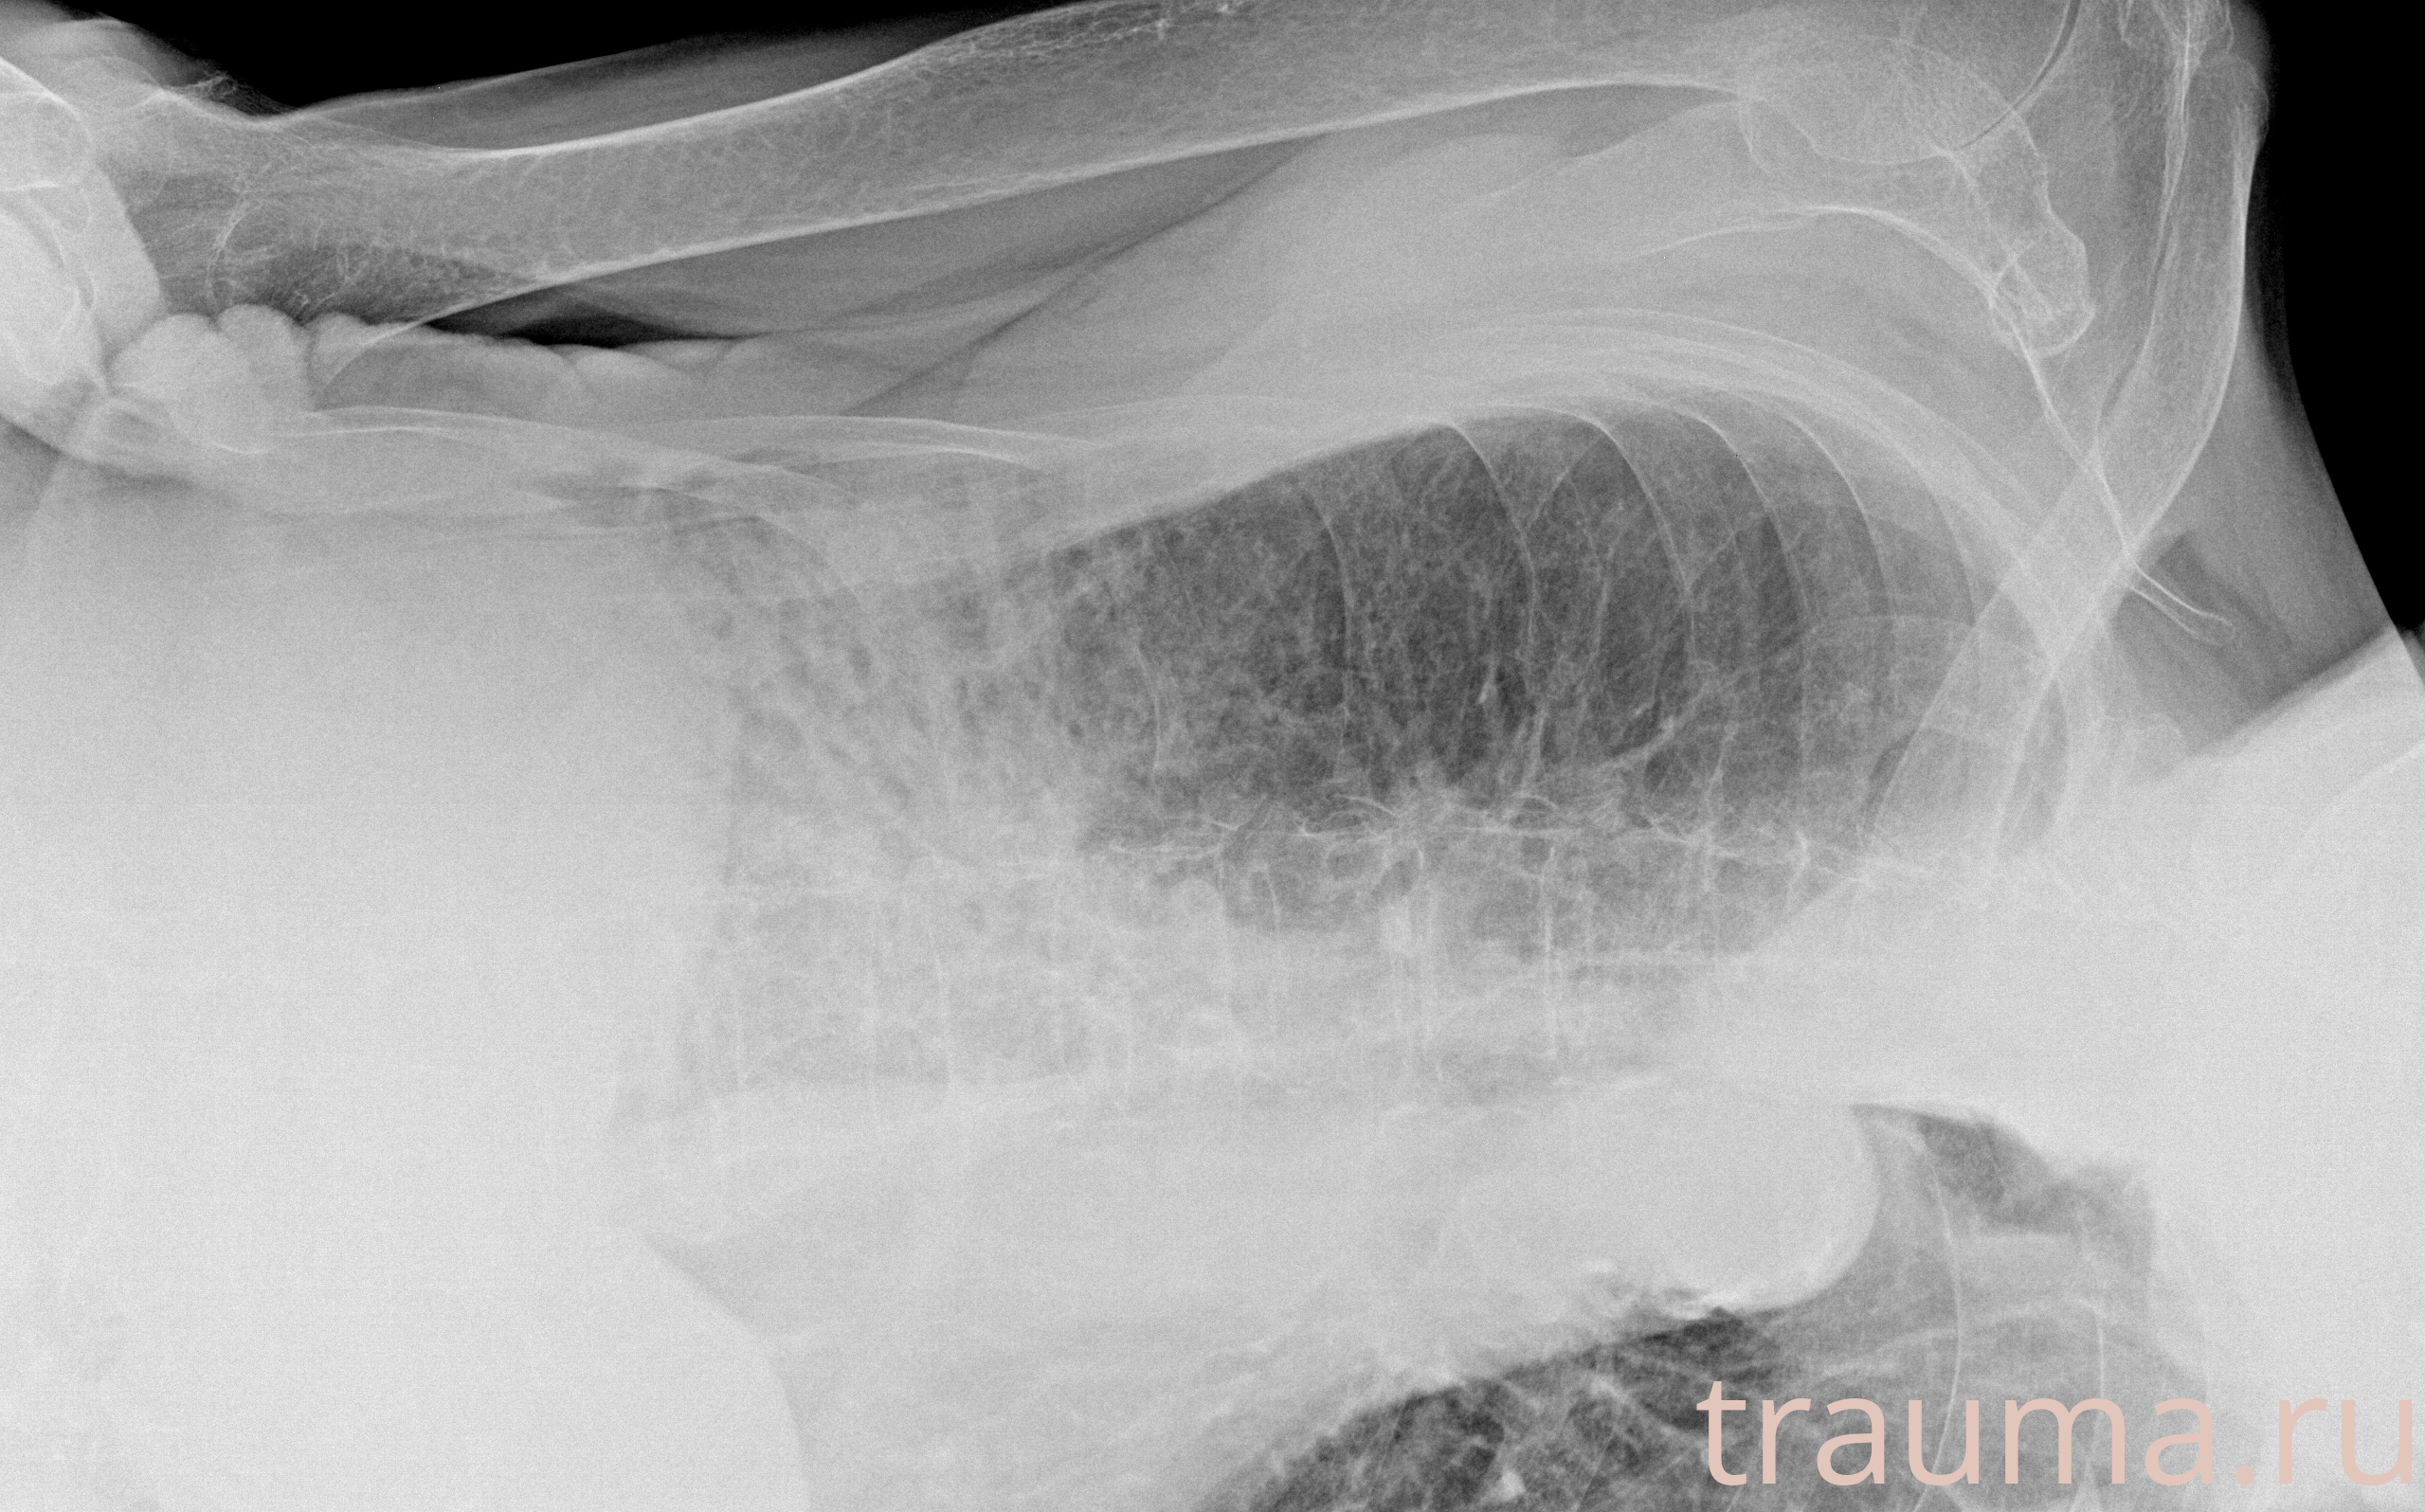

Рентген на дому: по вашему адресу приезжает врач-рентгенолог, травматолог-ортопед с мобильным рентгеновским аппаратом, проводит диагностику травмы или заболевания, делает необходимые рентгенограммы, дает рекомендации по дальнейшему лечению. Получить качественные снимки в домашних условиях возможно благодаря уникальной методике, разработанной МосРентген Центром для института  Склифосовского